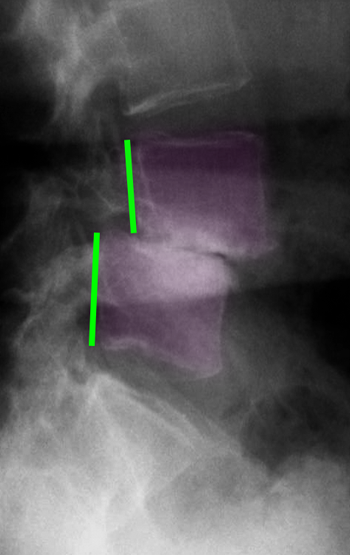

Εκφυλιστική σπονδυλολίσθηση Ο4-Ο5. Πλήρης σχεδόν εκφύλιση του μεσοσπονδυλίου δίσκου με καθίζηση του μεσοσπονδυλίου διαστήματος. |